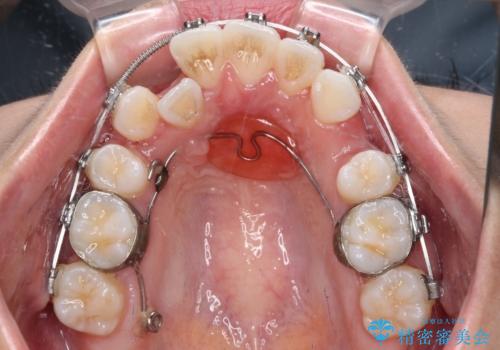

- メタルブラケット

口元の突出感は気にしていなかったため、上顎の左右第一小臼歯を抜歯することで、八重歯の解消と上顎の正中を改善していくこととしました。

奥歯の咬み合わせを維持しながら正中位置を改善するために、補助装置を使用しました。

予定より期間がかかりましたが、上下の正中位置を綺麗に一致させることができました。